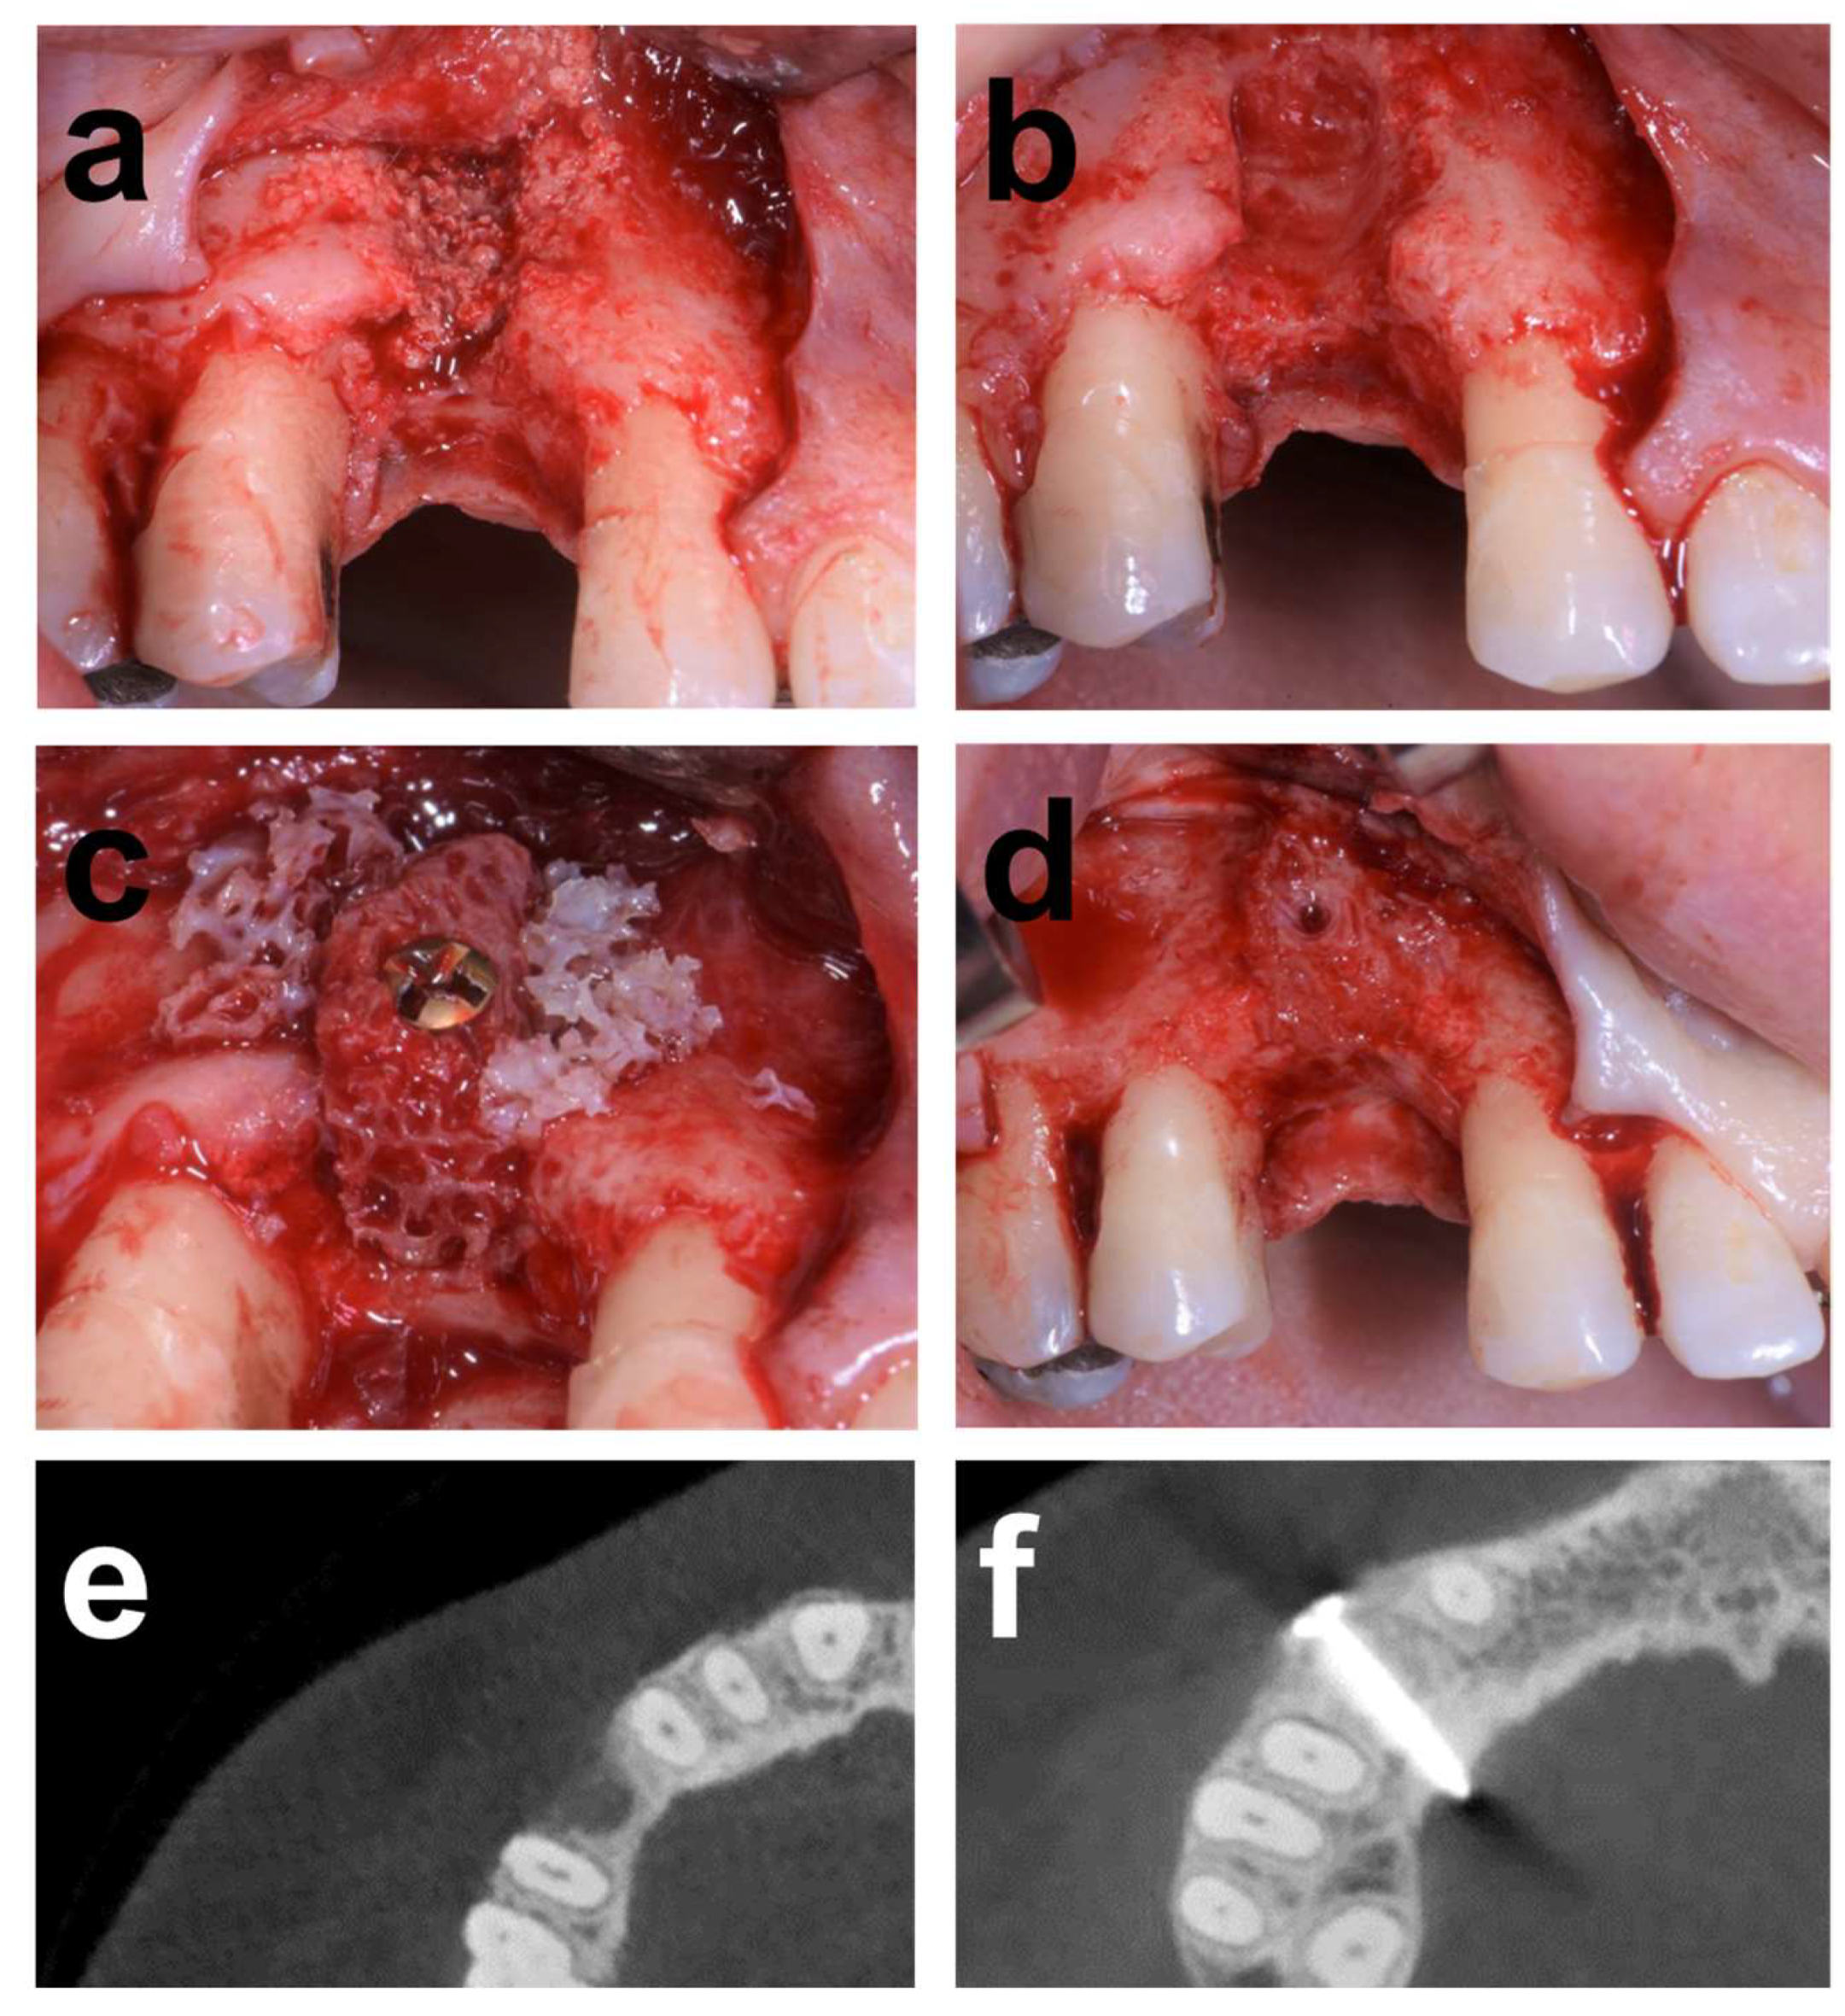

2.7.1. Case 1

2.7.2. Case 2

2.7.3. Case 3